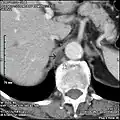

Scanner lombaire: Citerne du chyle (flèche pleine) à proximité de la veine azygos (flèche vide).

La citerne du chyle est un sac dilaté de 2 à 3 cm de diamètre situé dans la partie inférieure de la partie abdominale du conduit thoracique en regard de la deuxième ou de la troisième vertèbre lombaire en arrière de l'aorte abdominale.